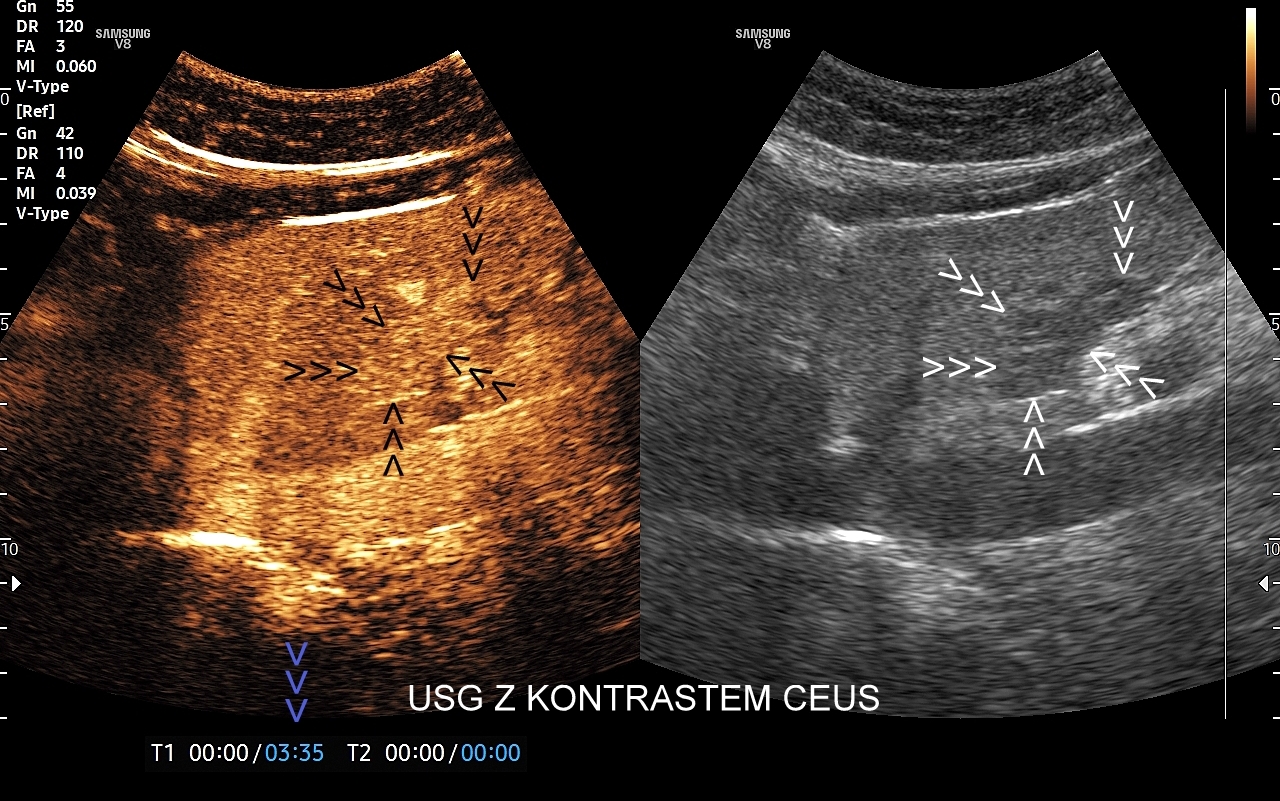

Badanie USG z kontrastem najczęściej wykorzystuje się do oceny zmian ogniskowych w wątrobie, potocznie nazywanych guzami wątroby, z których wiele ma na tyle specyficzny obraz mikrounaczynienia w obrazowaniu CEUS, że możliwe jest uniknięcie konieczności badania obciążającymi metodami TK lub MRI. Badanie CEUS w przeważającej większości pozwala odpowiedzieć, czy zmiana ogniskowa wątroby ma cechy złośliwe czy łagodne. Dodatkowo CEUS jest pomocny do wykrywania przerzutów do wątroby pochodzących z nowotworów w innej lokalizacji. W przypadku przerzutów o wielkości mniejszej niż 1 cm CEUS ma większą czułość aniżeli badanie TK.

CEUS jest badaniem w czasie rzeczywistym pozostającym pod kontrolą operatora, podczas którego możliwe jest wykonanie próby czynnościowej oraz natychmiastowe powtórzenie całego badania w razie konieczności. Możliwości takich nie dają ani TK ani MRI. Dodatkowo CEUS cechuje się o wiele większą rozdzielczością czasową w porównaniu do wspomnianych metod, co umożliwia uwidocznienie wczesnej fazy tętniczej unaczynienia podejrzanej onkologicznie zmiany ogniskowej w wątrobie i jej lepszą charakterystykę.

Przed właściwym badaniem na lewej kończynie górnej zakładana jest kaniula dożylna (tzw. Venflon). Badanie CEUS wykonywane jest w asyście pielęgniarki, która na sygnał lekarza podaje dożylnie kontrast. Po wstrzyknięciu kontrastu pacjent przez kilka minut pozostaje nieruchomo na leżance, podczas gdy lekarz trzymając stabilnie głowicę USG nagrywa poszczególne fazy unaczynienia diagnozowanej zmiany chorobowej. Po zarejestrowaniu filmów lekarz analizuje ich zawartość. Wyniki badania wydawane są zwykle w ciągu jednego do dwóch dni, lecz nie od razu po zakończeniu badania. Pobyt pacjenta w przychodni w związku z badaniem CEUS wynosi ok. godziny.